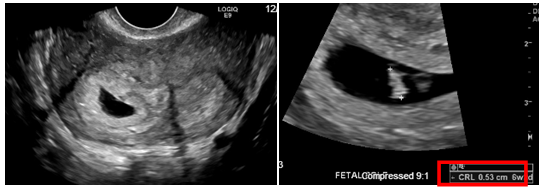

A 24-year-old Hispanic female, G1P0 at 6 4/7 weeks gestational age, presented for her first prenatal visit. Bedside ultrasound showed a second mass next to the uterus and official ultrasound revealed duplicated uterine horns and cervices with a single live intrauterine pregnancy within the right uterine horn (Figure 9). Differential diagnosis includes uterine didelphys and bicornuate bicollis uterus. However, the patient declined pelvic MRI for further evaluation of didelphys uterus, despite counseling on the safety of MRI during pregnancy.

Figure 9 Patient 3: Pelvic Ultrasound: Differential diagnosis includes uterine didelphys and bicornuate bicollis uterus. Single live intrauterine pregnancy within the right uterine horn corresponding to a sonographic age of 6 weeks 2 days noted.

In all three cases pelvic ultrasound was initial imaging tool. The ultrasound in case 1 (Figure 1) and subsequent MRI (Figure 2) shows a lobular tubular thick wall cystic structure in the right pelvis suggesting hemorrhagic contents extending into the right aspect of the posterior vagina and didelphys uterus. MRI of the abdomen depicts renal agenesis, demonstrating abnormal kidney development confirming HWW. As per the classification presented by Zhu and imaging, the patient has a class 1.2 OHVIRA.2 The ultrasounds in cases 2 and 3 (Figures 6 & 9 respectively) both demonstrate didelphys uterus with two cervices. The additional MRI in case 2, revealed two separate cervices and two uteri one with a retained IUD. MDA can be associated with a vaginal septum, more commonly vertical (Case 2 & Figure 5) but cases of a horizontal septum have also been reported (Case 1 & Figure 8).14